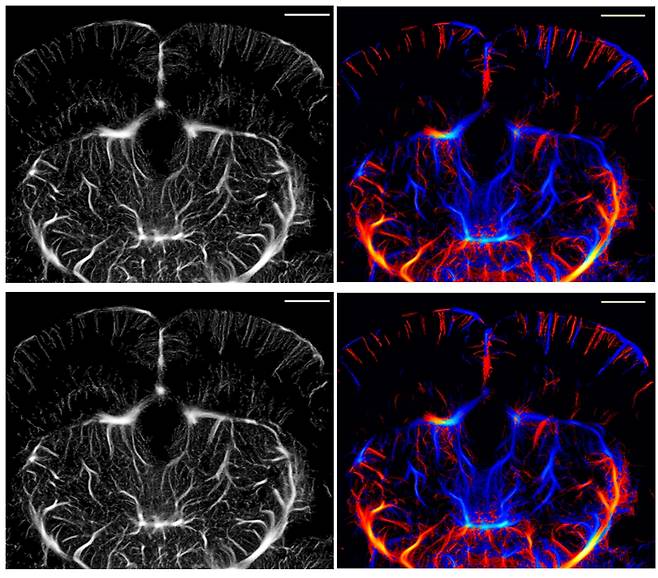

![기존 ULM으로 획득한 쥐 뇌 모세혈관 영상(위)과 개발된 ULM-Lite 기법으로 획득한 모세혈관 영상(아래).[DGIST 제공]](https://img3.daumcdn.net/thumb/R658x0.q70/?fname=https://t1.daumcdn.net/news/202511/18/ned/20251118092749048crmt.jpg)

연구팀은 이러한 문제를 해결하기 위해, 초음파 신호 중 핵심 정보만 남기고 불필요한 데이터를 과감히 줄이는 새로운 분석 방식을 고안했다. 연구팀은 신호의 ‘유효 대역폭’을 약 67%로 줄이고, 혈관의 구조를 그리는 데 꼭 필요한 정보만 효율적으로 추출하는 ‘ULM-Lite’ 방식을 고안했다. 그 결과, 데이터 용량은 줄었지만 영상의 선명도는 거의 변함이 없었고, 처리 속도는 훨씬 빨라졌다.

이번 연구의 핵심은 기존 초음파 장비를 그대로 쓰면서도 데이터를 크게 줄였다는 점이다. ‘ULM Lite’는 초음파 신호 중 꼭 필요한 정보만 남겨 데이터량을 약 3분의 1로 줄였지만, 화질은 기존과 거의 같다. 별도 장비 교체 없이 적용할 수 있고, 영상 처리 속도도 약 30% 빨라졌다. 또 수술이나 형광물질 없이 비침습적으로 뇌 전체를 선명하게 볼 수 있어, 뇌 연구와 질환 진단의 효율성을 크게 높였다. 뇌의 자극 치료와 행동 변화 관찰을 위한 도구로 활용 가능성이 높다.